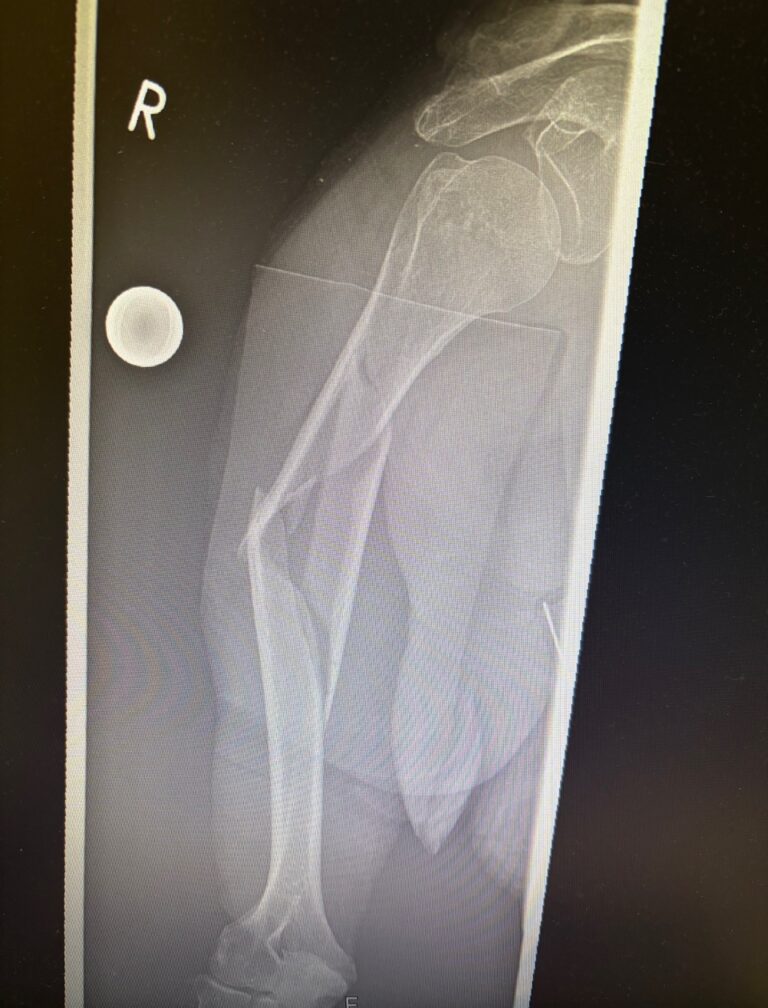

- Κάταγμα διάφυσης βραχιονίου

- Ακτινογραφία

- Αξονική / Μαγνητική (σε σύνθετα κατάγματα)